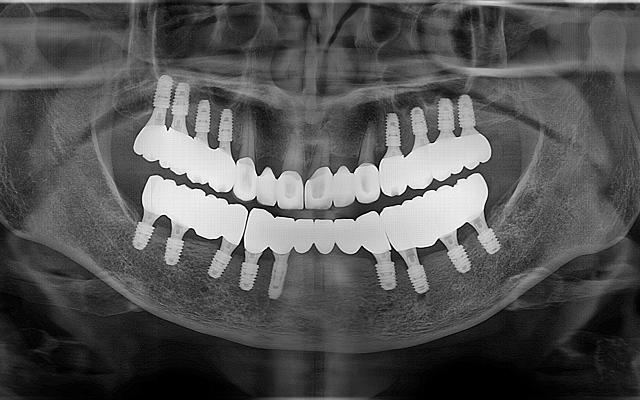

전악 케이스

- 상·하악 전체 보철 설계를 통해 정확한 교합(물림) 회복

- 심미·발음·저작 기능을 종합 고려한 자연스러운 전악 임플란트